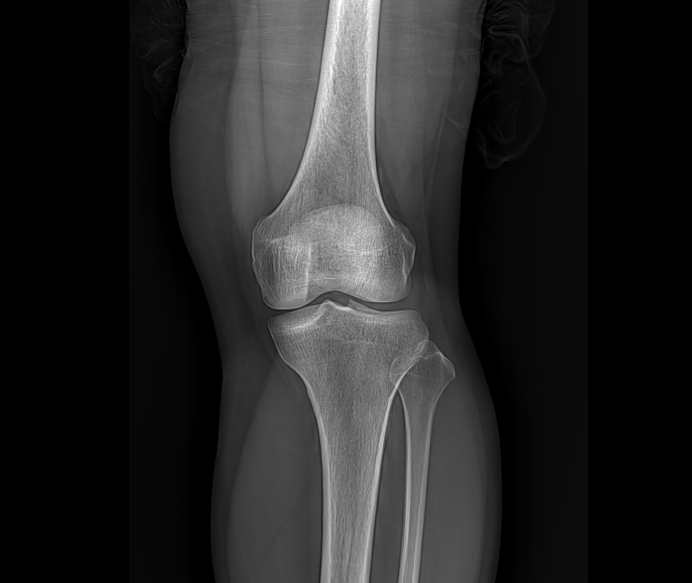

• Clinical Images